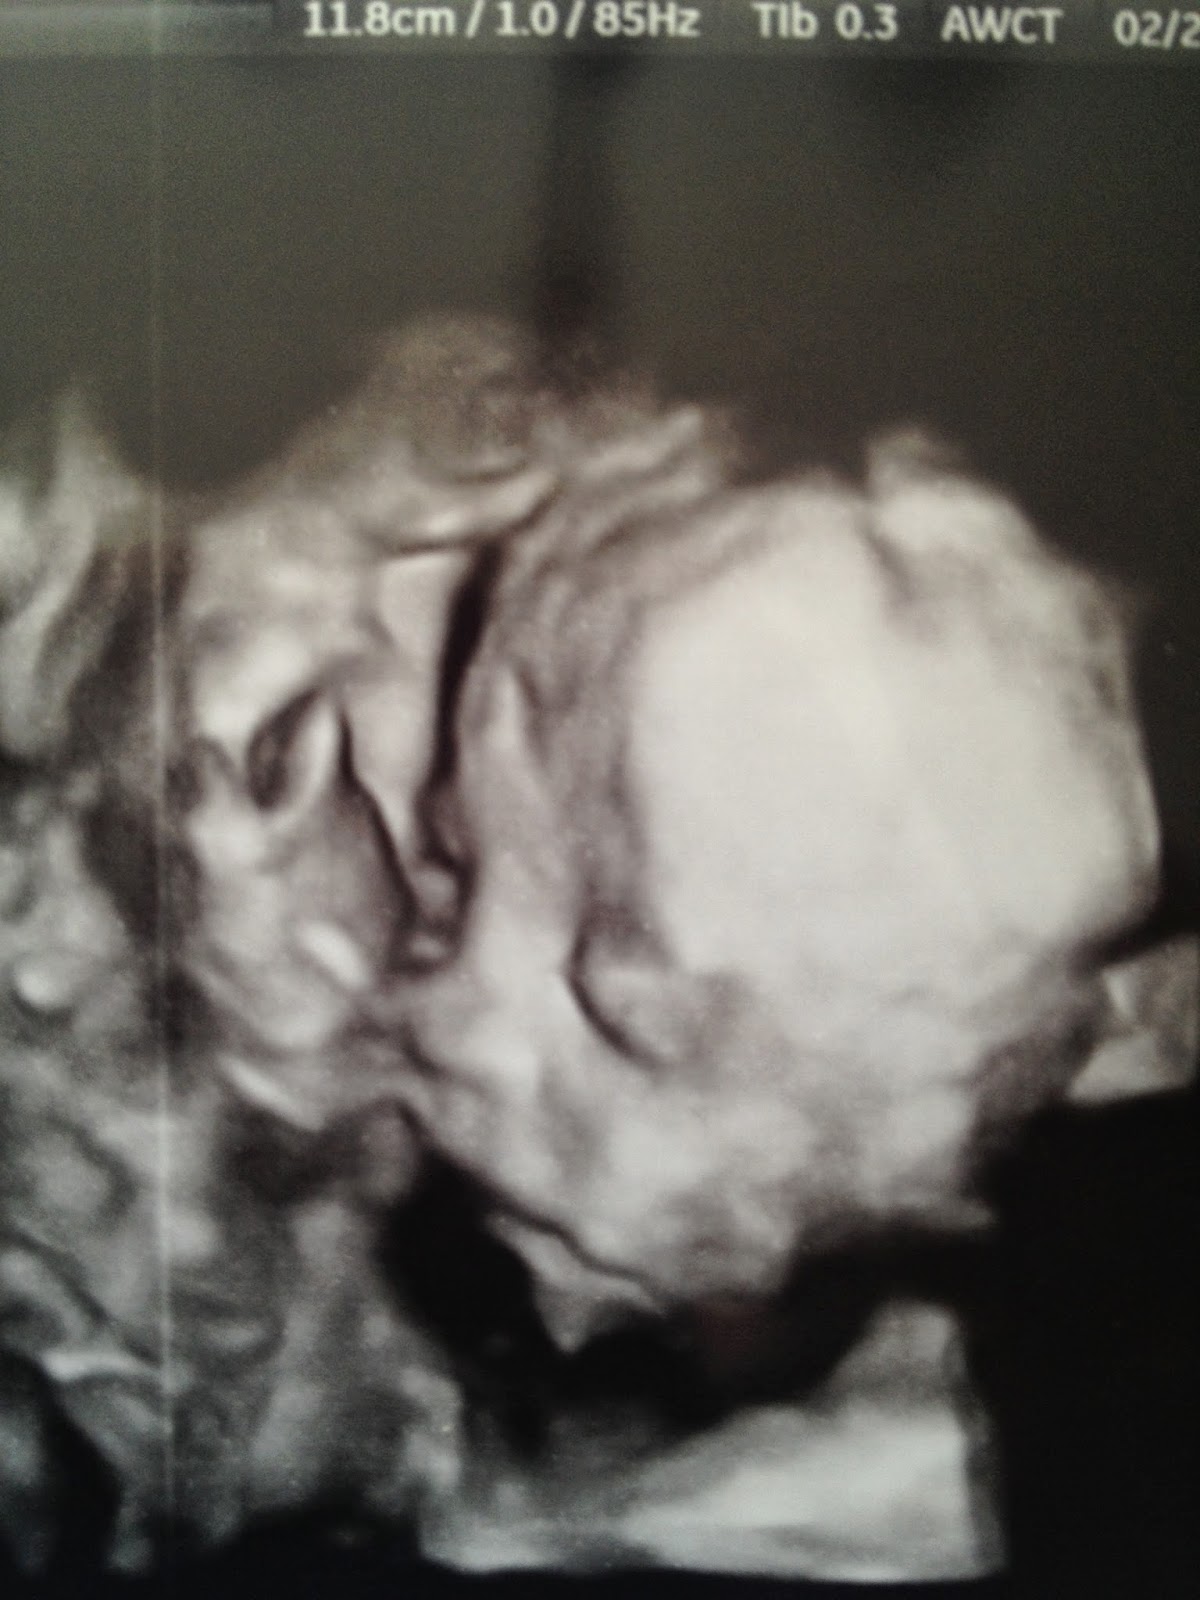

After the scan and measurements they said "she seems to be measuring according to her due date, except for her head. Her head's measuring really large." I must've had quite the look on my face because she quickly said "no, it's ok, she's perfectly fine, there are no problems, just a big head." To which I said I know and understand, look at her father's, that' s what I'm worried about on labor day! She very quietly giggled and said "I'm sorry." Great. But it was so fun to get to see our babe (and nice to not have terminator show up again!):

And since then? The gymnast has not stopped moving. It's as if she's saying "oh you were complaining about me moving? Fine, I'll show you" and has been at it ever since. While becoming increasingly uncomfortable, I love it all the same!